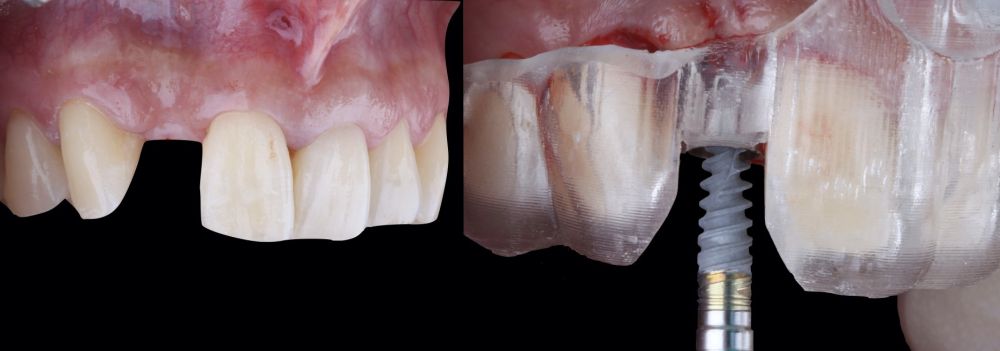

* Phase II: healing proceeded without complications. After 5 months from the alveolar preservation surgery, guided implant surgery was planned at position 1.2 (Figure 2). For this purpose, a DICOM file from cone beam computed tomography (CBCT) and an STL file obtained from scanning with an intraoral optical scanner were used. Using this information, a dental support surgical guide was fabricated (Figure 3). The surgical guide was anchored onto the teeth and guided the preparation of the implant bed and the placement of the implant. The guided surgery technique consisted of flap surgery, preparing and inserting the implant (3.5 x 11.5 mm) according to the standardised Nobel Active® guided surgery protocol (Nobel Biocare AB, Gothenburg, Sweden). Once implant 1.2 was placed,a gingival graft composed of epithelium and connective tissue from the palatal masticatory mucosa was obtained. Subsequently, the superficial epithelial layer of this graft was deepithelialised extraorally using a 15C scalpel blade in order to obtain a connective tissue graft from the underlying layer18.

The de-epithelialised graft was inserted and

positioned buccally and occlusally using horizontal mattress sutures with 5-0 non-resorbable suture (Figure 4)19.